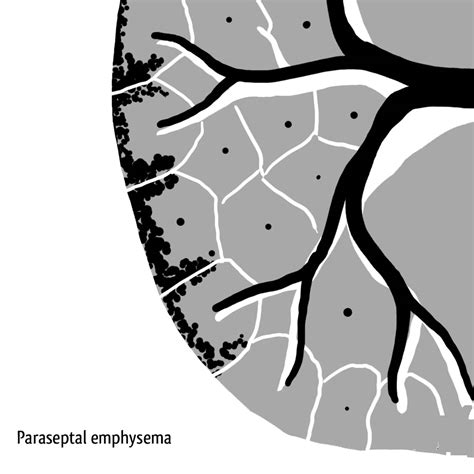

• 4 types of emphysema